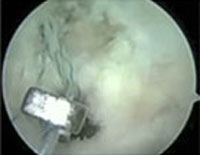

PCL Reconstruction Surgery is typically done as an outpatient procedure. Depending on graft choice, open incisions may be necessary to harvest the tissue that is to be used as the new PCL. Knee Arthroscopy is then performed to inspect the knee, treat additional knee injuries (meniscus tears or cartilage damage), and to prepare the knee for the new PCL.

Once the graft tissue has been prepared and the torn PCL Tissue has been removed, the surgeon is ready to place the ligament within the knee. Small tunnels (7-10 mm) are drilled in tibia and femur to allow the ligament to be pulled up into the Knee.

Accurate placement of these tunnels is critical to success of the PCL Reconstruction Surgery. After the PCL graft is in position, fixation devices (screws, washers, buttons, etc.) are used to keep it there until it can heal the place.

- The Knee Surgeon in Mumbai inspects the knee and may or may not remove the remains of the old PCL.

- After harvesting the tissue, a hole is drilled from the front of tibia diagonally into the Knee and ends up where the PCL attaches to the top of the shin. Next, the Arthroscopic Knee Surgeon drills a hole in femur between the two heads running diagonally and up from the middle to the outside. The Posterior Cruciate Ligament Surgery differs from the Arthroscopic Knee Surgery in that additional posteromedial Portal is made in Posterior Cruciate Ligament Surgery to view the back of the Knee from where the PCL comes out from tibia.

- The harvested replacement graft is pulled into place through the holes which were just drilled.

- The new ligament is then held into place by two bioabsorbable screws or metallic screws.